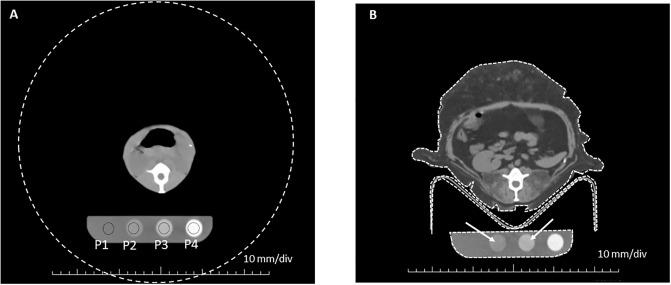

We developed a method to quantify fibrosis by subject size-adjusted CT Hounsfield units. This was accomplished using CT measurements of renal cortex in previously irradiated non-human primates.

Renal cortex mean CT Hounsfield units that were adjusted for body size had a very good direct correlation with renal parenchymal fibrosis, with an area under the curve of 0.93.